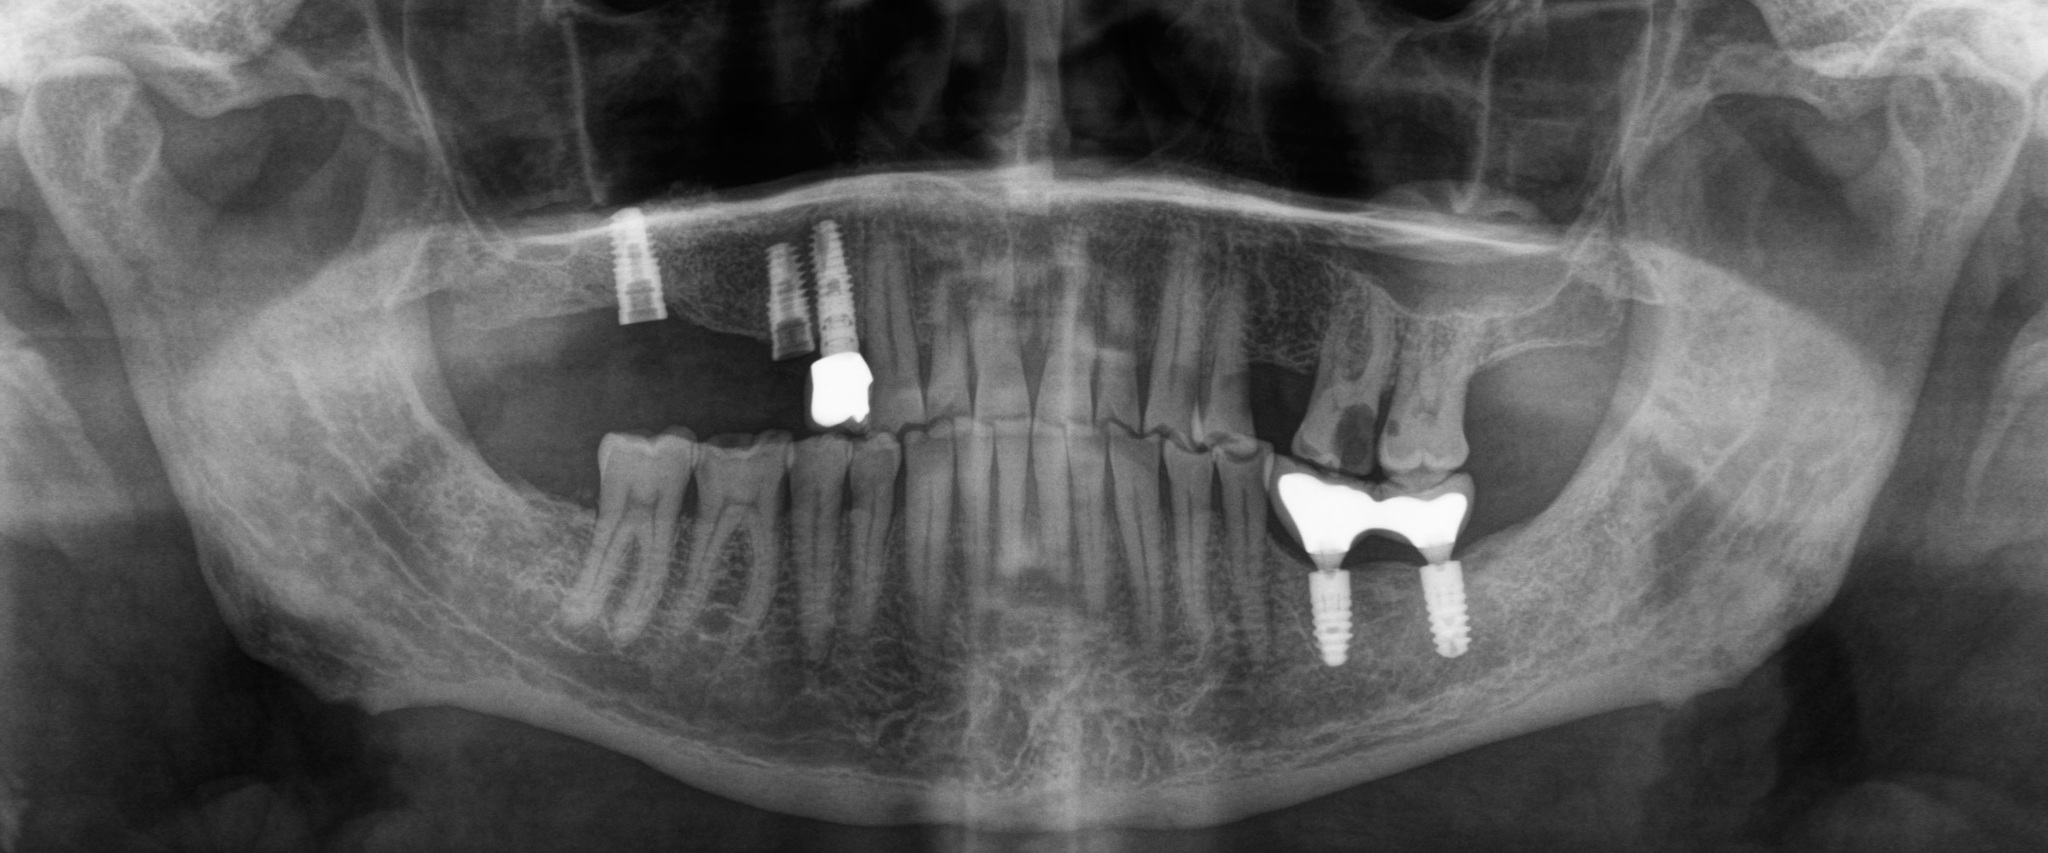

Первым контрольным рентгеновским снимком был этот:

На установленных ранее имплантатах в области 5 и 7 зубов на верхней челюсти справа (на снимке слева) стоял временный мостовидный протез. Пластик, из которого изготовляются временные конструкции не рентгеноконтрастен. Поэтому ничего кроме «белых полосок» в этой области вы не увидите. Средний срок службы подобных конструкций три месяца, но «по семейным обстоятельствам» пациент пользовался ими дольше обычного. Это привело к тому, что мостовидный протез треснул, аки старый трухлявый деревенский мост. В связи с этим, собственно, пациент и явился на прием. Напомню название статьи – «бруксизм». Сложно не заметить отсутствие зубов на противоположной стороне челюстей. Отсюда можно сделать логичный вывод, что основное (если не единственное) пережевывание пищи осуществлялось на стороне, где установлены имплантаты.

Разницу в материалах можно видеть по белым полоскам в месте, где должна быть коронка. Если обычную временную коронку не видно, то при наличии металла на рентгеновском снимке его будет отчетливо видно.

Рентгеновский снимок после извлечения винта и снятия мостовидно протеза:

Временным (!) решением данной проблемы была замена фиксирующего винта на новый и фиксация этого же мостовидного протеза на место: